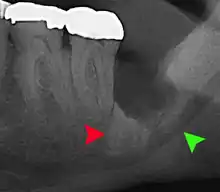

Long-term complications can include periodontal complications such as bone loss on the second molar following wisdom teeth removal. Bone loss as a complication after wisdom teeth removal is uncommon in the young but present in 43% of those of 25 years of age or older.[22] Injury to the inferior alveolar nerve resulting in numbness or partial numbness of the lower lip and chin has reported rates that vary widely from 0.04% to 5%.[22] The largest study is from a survey of 535 oral and maxillofacial surgeons in California, where a rate of 1:2,500 was reported.[25]

Coronectomy

Coronectomy is a procedure where the crown of the impacted wisdom tooth is removed, but the roots are intentionally left in place. It is indicated when there is no disease of the dental pulp or infection around the crown of the tooth, and there is a high risk of inferior alveolar nerve injury.[31]

Coronectomy, while lessening the immediate risk to the inferior alveolar nerve function has its own complication rates and can result in repeated surgeries. Between 2.3% and 38.3% of roots loosen during the procedure and need to be removed and up to 4.9% of cases require reoperation due to persistent pain, root exposure or persistent infection. The roots have also been reported to migrate in 13.2% to 85.9% of cases.[31]